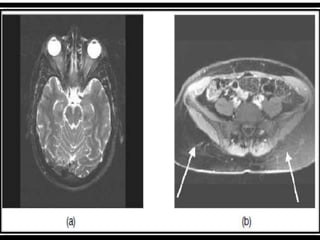

DIFFUSION WEIGHTED IMAGING (DWI)

• MR imaging based upon measuring the random Brownian motion of

water molecules within a voxel of tissue.

• Densely cellular tissues or those with cellular swelling exhibit lower

diffusion coefficients

• Particularly useful in tumour characterisation and cerebral

ischaemia